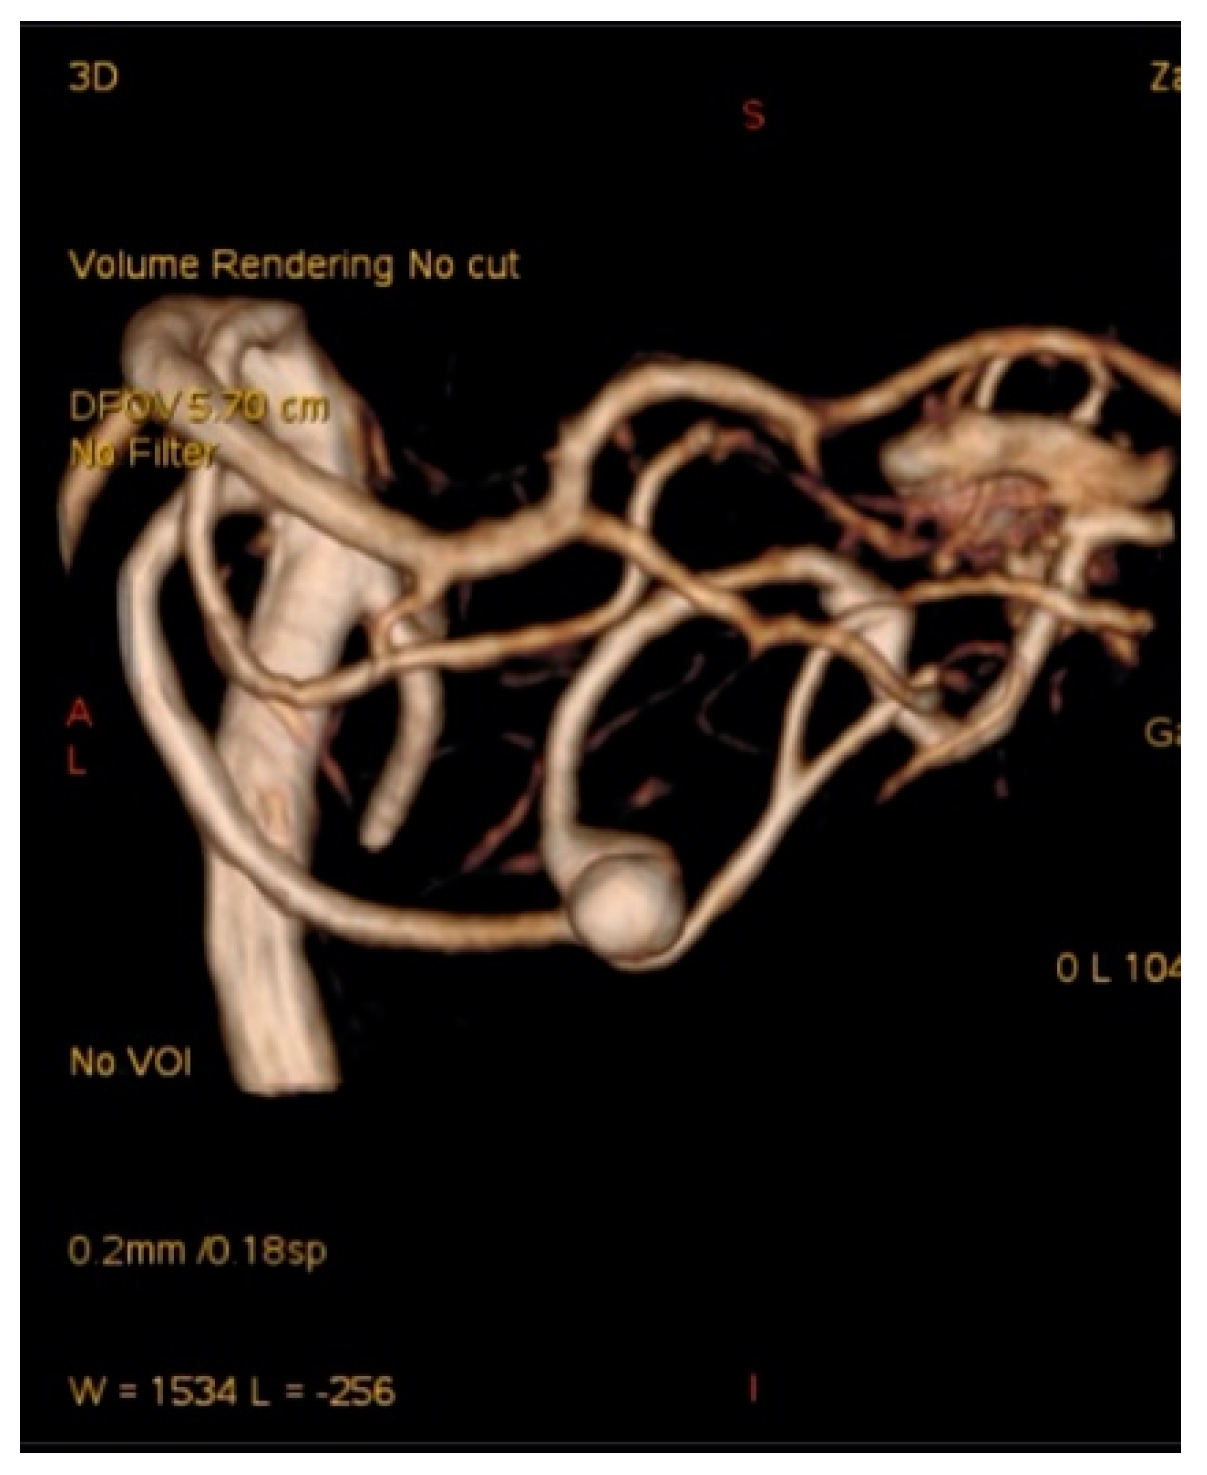

A 57-year-old female hypertonic patient was admitted to the neurology unit of a regional hospital in a mild Hunt and Hess grade for sudden-onset headache and vomiting. Computed tomography (CT) confirmed Fischer grade 2 subarachnoid hemorrhage (SAH). Following atypical angiography findings, an aneurysm on the bifurcation of the basilar artery (BA) was suspected (Figure 1), and the patient was urgently referred for endovascular treatment. Following catheter placement and 3 Dimensional—Digital Subtraction Angiography imaging, an aneurysm on the peripheral branch of the SCA was found, which was inaccessible for endovascular treatment due to the luminal diameter of the vessel. An additional MRI confirmed the suspected location and gigantic size of the partially thrombosed lesion, and the patient was prepared for surgery. With a midline supracerebellar approach, trapping of the parent artery and extirpation of a large (15 × 18 mm) thrombosed sac with preservation of the precentral vein were performed. Histological findings were without surprise; no mycotic agents or bacterial inflammation in the aneurysmal wall were revealed. Her postoperative course was uneventful, and follow-ups are undertaken every year.

Figure 1. Angiogram misdiagnosed as aneurysm of bifurcation of the basilar artery (BA) in case report 1.